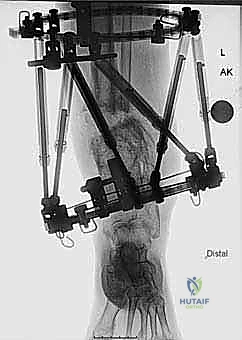

- التميز في التثبيت الخارجي (Ilizarov & TSF): يمتلك الدكتور هطيف مهارة استثنائية في استخدام أجهزة التثبيت الخارجي الدائرية (مثل جهاز إليزاروف وجهاز تايلور المكاني)، وهي أجهزة تتطلب عقلاً هندسياً وحسابات رياضية دقيقة لضمان تصحيح العظم بالمليمتر والدرجة.

المرحلة الثانية: تركيب المثبت الخارجي (Frame Application)

قبل قطع العظم، يقوم الدكتور هطيف بتركيب الهيكل الخارجي (الإليزاروف أو الفريم الدائري).

1. يتم إدخال أسلاك دقيقة جداً (K-wires) ومسامير نصفية (Half-pins) عبر الجلد إلى العظم بدقة متناهية لتجنب الأعصاب والأوعية الدموية.

2. يتم تثبيت هذه الأسلاك في الحلقات المعدنية الخارجية. حلقة أو حلقتين فوق مكان القطع المخطط له، وحلقة تحته (في الجزء السفلي من الساق والقدم إذا لزم الأمر).

3. يتم التأكد من استقرار الهيكل الخارجي بالكامل.